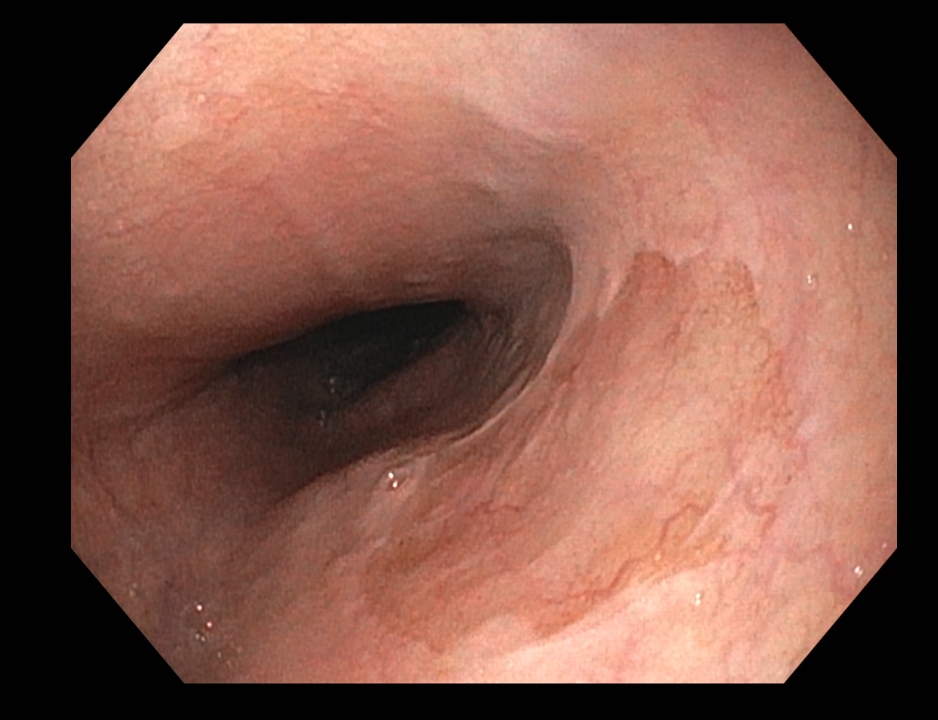

식도 상부에서 전형적으로 발견되는 위점막과 닮은 구별되는 영역. 일반 인구에서 유병률은 autopsy에서 약 5%인 반면 위내시경 연구에서는 상부위장관내시경을 시행하는 환자에서 0.4~11%. 내시경 연구에서 유병률이 더 낮은 이유는 inlet patches가 식도 상부에 위치하고 있기 때문인 것 같습니다. 가장 일반적으로는 UES 아래 식도 3 cm 부위에서 발견되며 이 부위는 일반적인 상부위장관내시경 동안에 잘 보여지는 곳은 아닙니다. Inlet patches는 모든 연령에서 기술되었지만 가장 일반적으로 발견되는 나이는 50대 중반입니다.